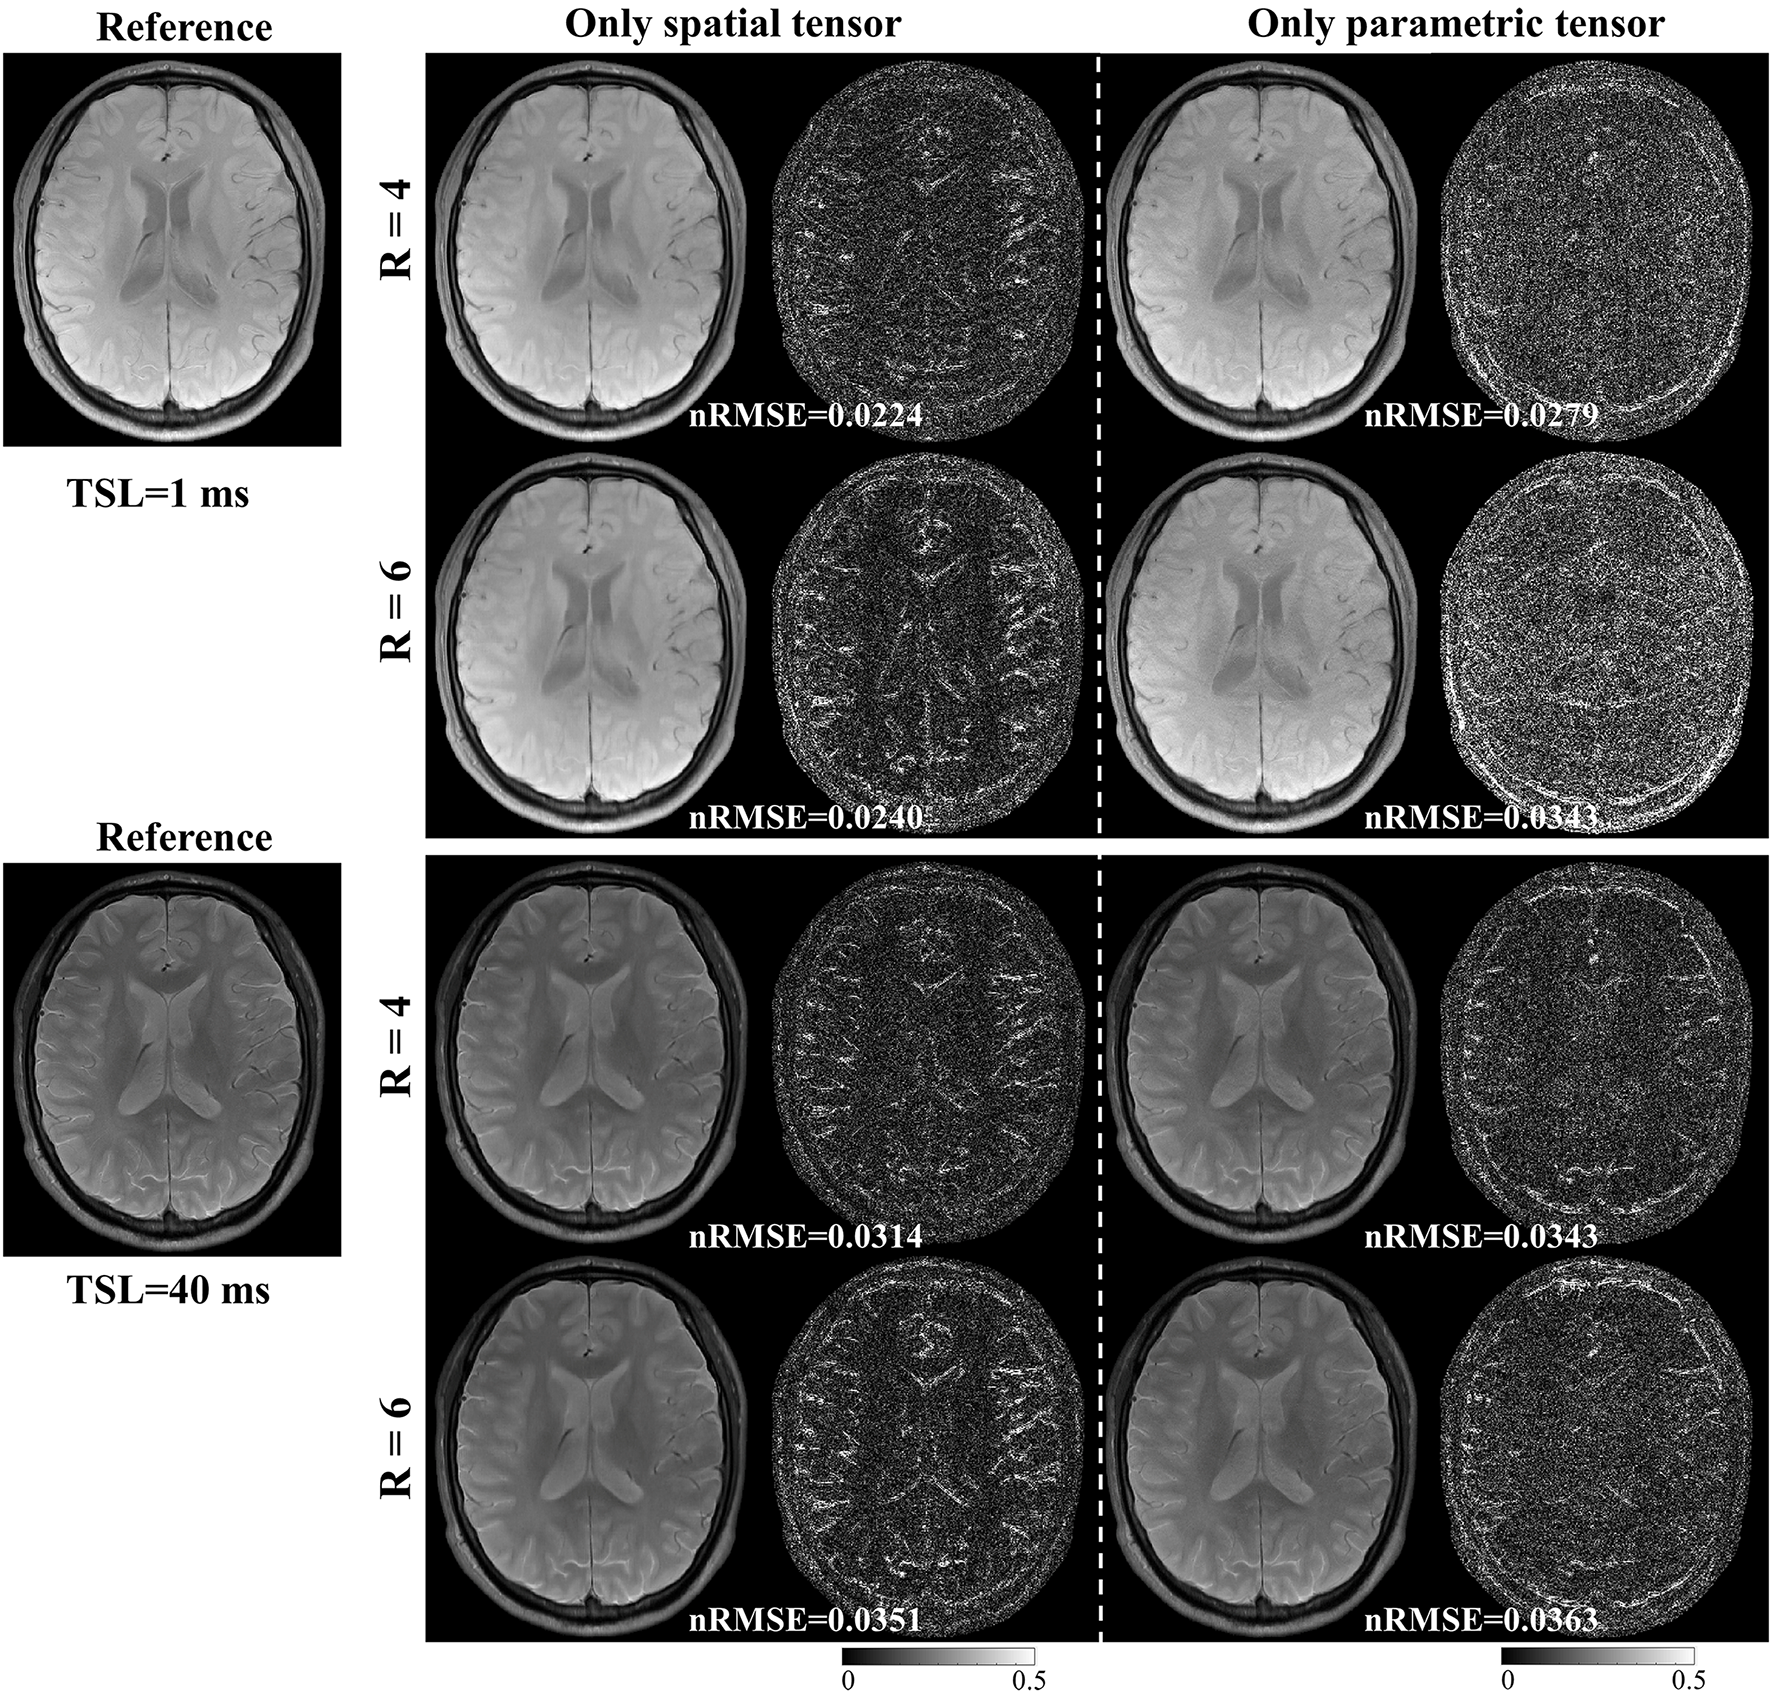

3.4 Ablation Experiment

We conducted an ablation study to analyze the spatial and parametric tensors’ effects on the reconstruction. Two models are constructed as follows:

model 1:

| (17) |

model 2:

| (18) |

Model 1 only includes the spatial tensor, and model 2 only includes the parametric tensor. Model 1 is the same as the PROST method. Similarly, we applied ADMM to solve the optimization problem in model 2. These two models were used to reconstruct images from the retrospectively undersampled in vivo dataset with R = 4 and 6.

4.6 Ablation Experiment

Fig. 10 shows the reconstructed images for models 1 and 2 with R = 4 and 6, respectively. For the results of model 1, the aliasing artifacts due to undersampling can be well removed from the reconstructed images by applying the spatial tensor, but the reconstructed images are blurry. In contrast, the sharpness of images reconstructed by model 2 is improved, but aliasing artifacts still exist. These results are in line with our hypothesis that the parametric group-based tensor can help improve image sharpness and preserve more image details in the reconstructions.